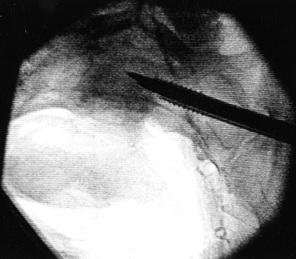

Position the guide wire relative to the spinal canal and the sacral promontory as seen on the inlet view (Fig. 28.12). The outlet view shows the pin’s position relative to the S-1 and S-2 foramina (Fig. 28.13).

Aim the guide wire to approach the sacral body in a

posterior-to-anterior direction from caudad to cephalad. As the guide

wire is advanced, check it frequently in both the inlet and outlet

views. The pin should cross the midline.

Figure 28.12. Inlet view of the pelvis, showing the guide wire central to the spinal canal and sacral promontory.